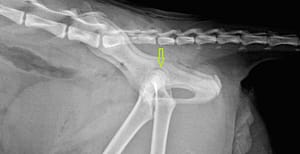

De foto hieronder laat zien dat de heup succesvol terug is geplaatst in de kom.